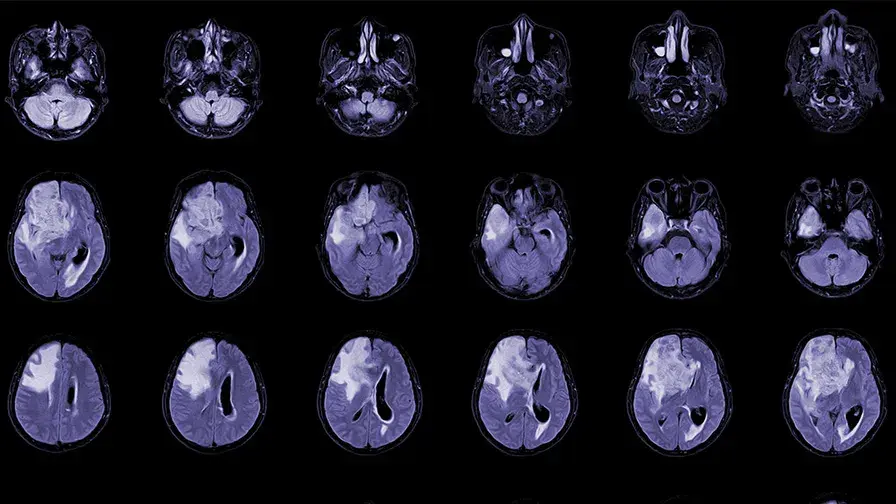

• IRM,vues axiales du cerveau